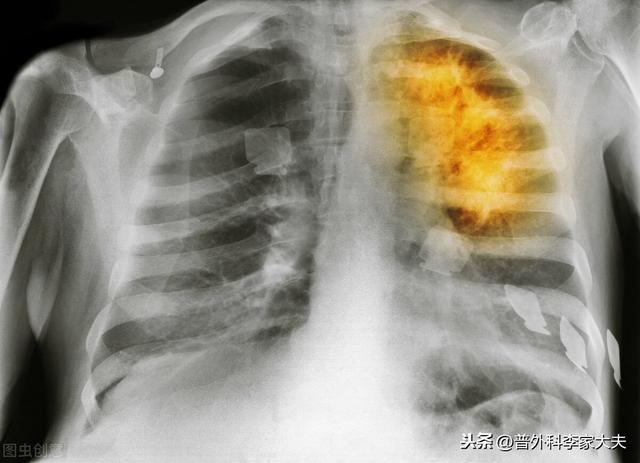

Patients atteints de cancer du poumon

chirurgie pulmonaire par thoracoscopie